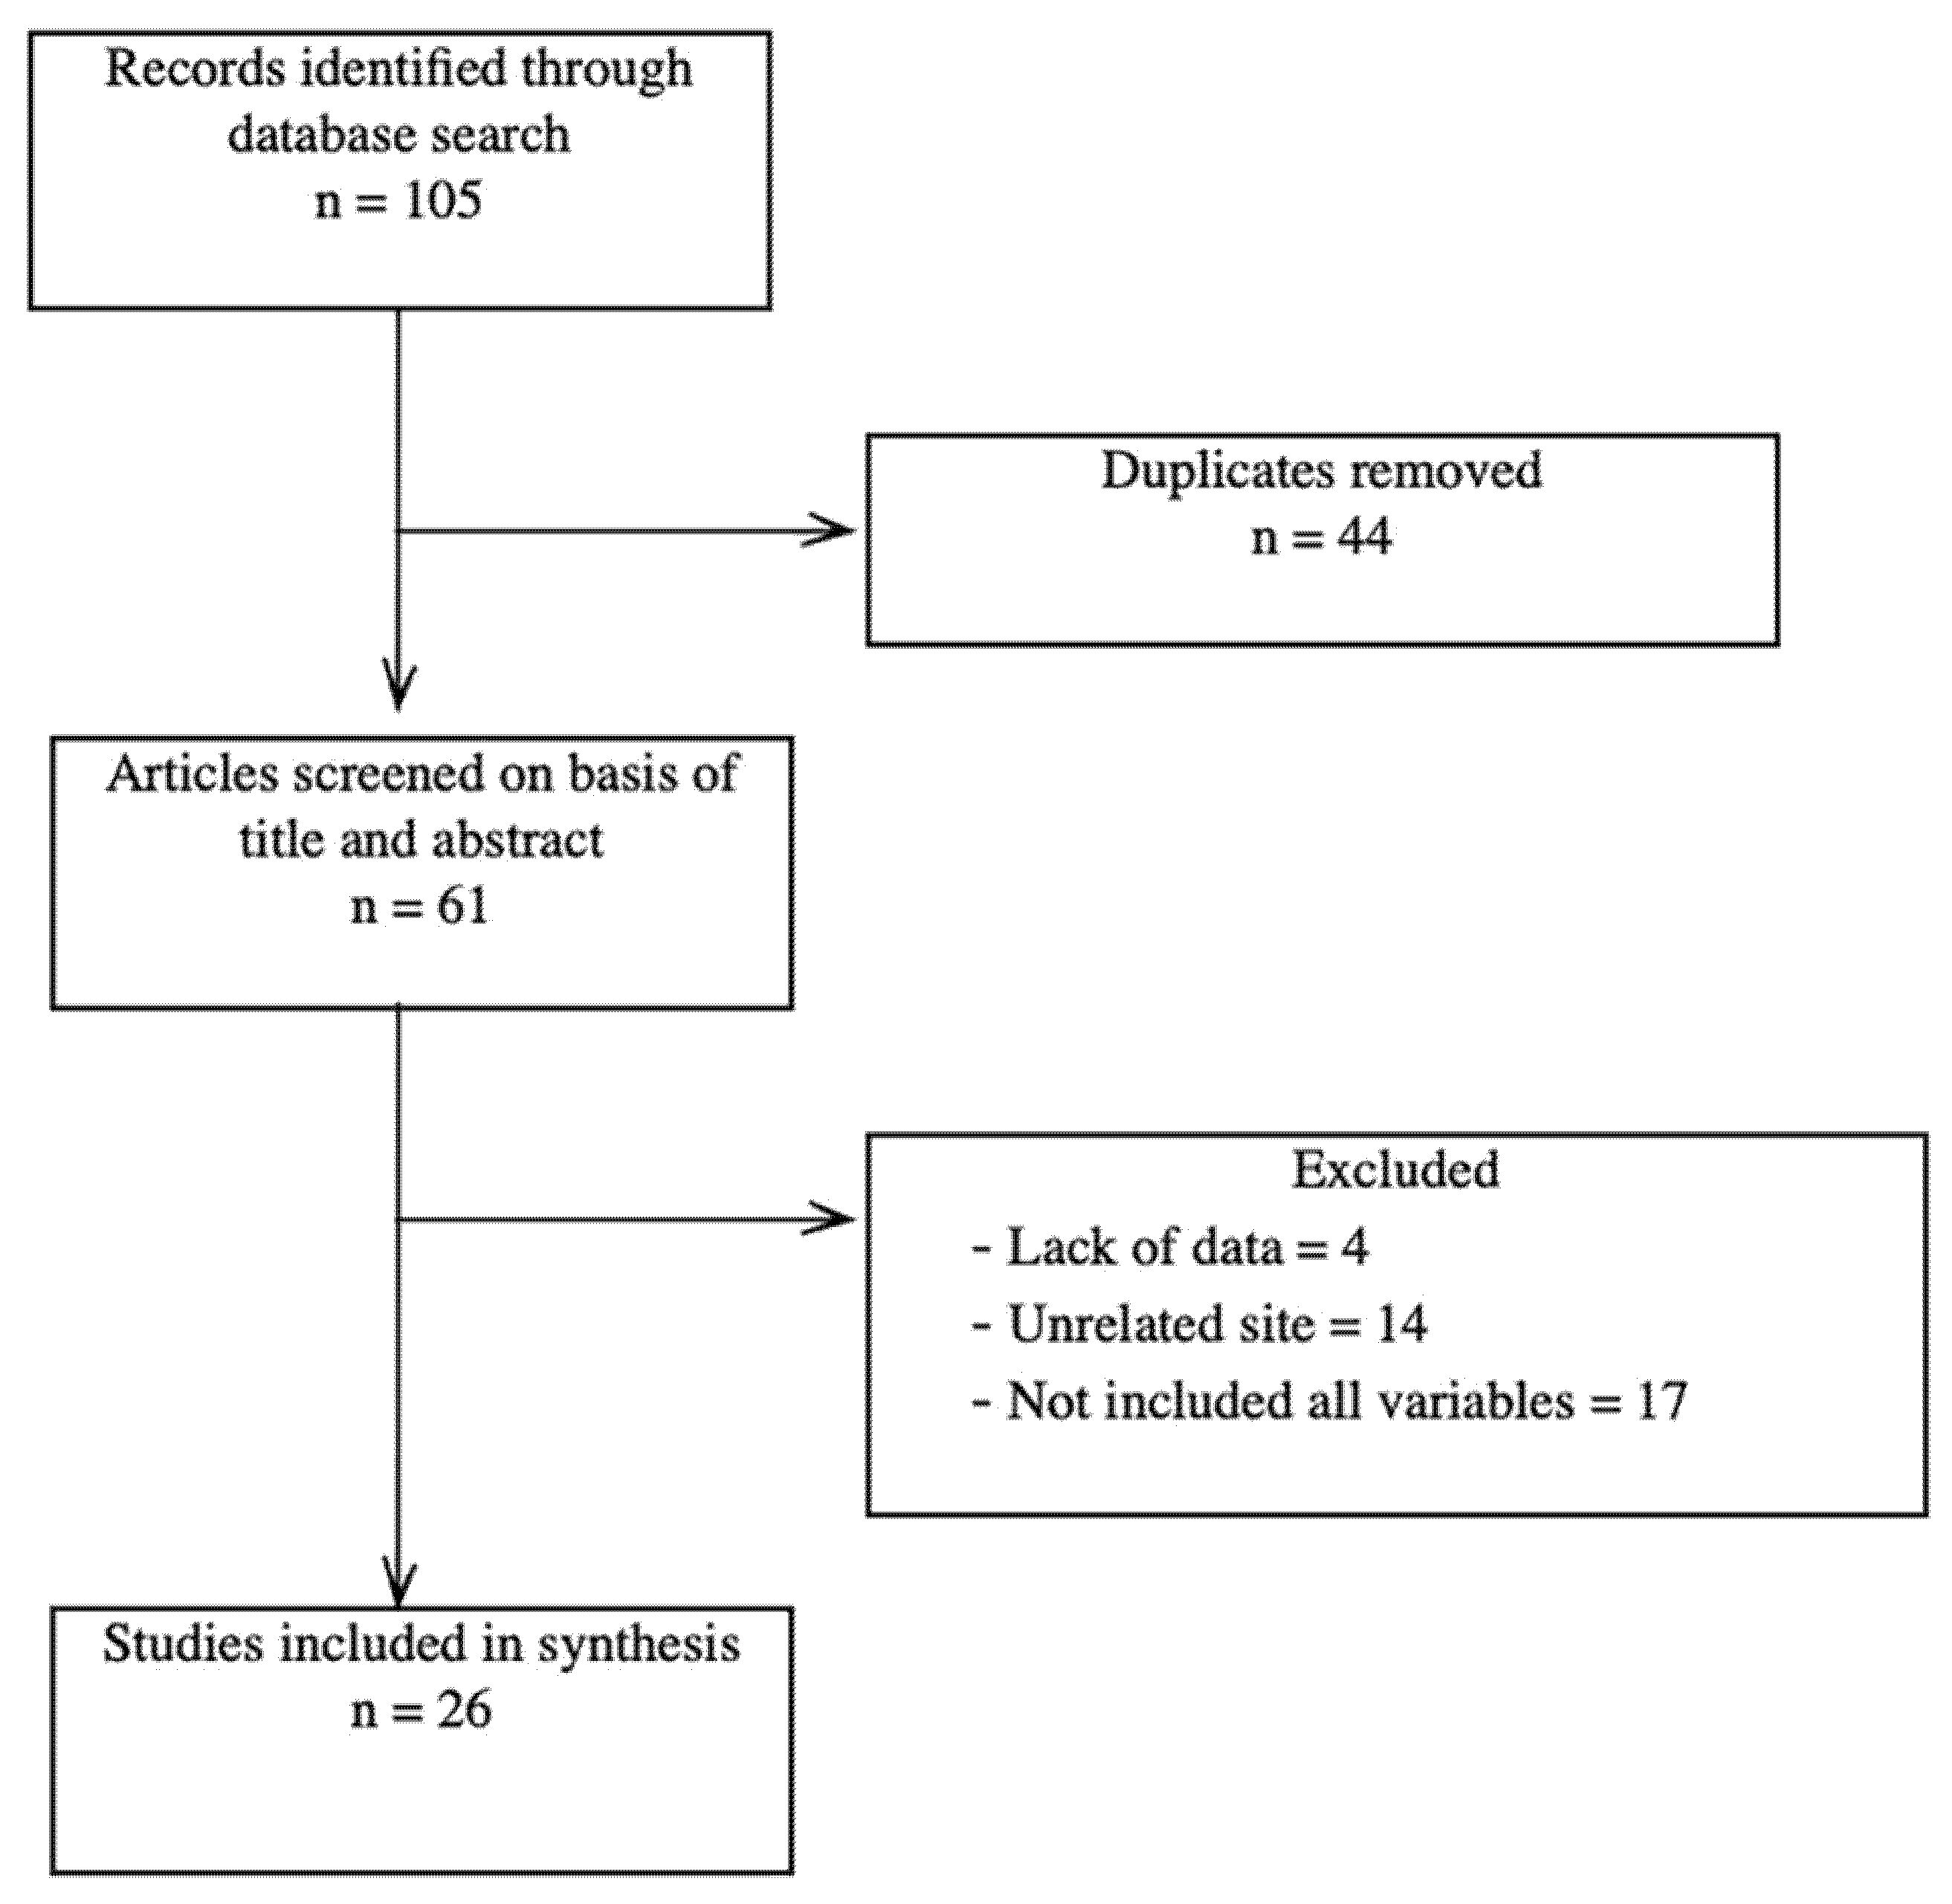

A literature review was performed by searching the PubMed database. The terms used for the search were brachial artery aneurysm, AVF ligation, and RT. The search was limited to any reported cases of brachial artery aneurysm formation in patients with RT and previous AVF ligation. The reports were selected according to the PRISMA guidelines. In the end, we selected 26 articles that matched all our keywords.

Figure 1 shows a PRISMA flow diagram for this review. We conducted PubMed and Medline database searches in the English language. The keywords we used were “brachial artery aneurysm”, “arteriovenous fistula”, “immunosuppressive treatment” and “renal transplantation”. After the removal of duplicates we screened 61 articles on basis of their titles and abstracts. We excluded 35 articles due to a lack of data (absence of AVF age, type of conduit used for vascular reconstruction, exact location of the aneurysm), an unrelated site of aneurysm formation, or due to the fact that they did not include all the variables (

Figure 1).